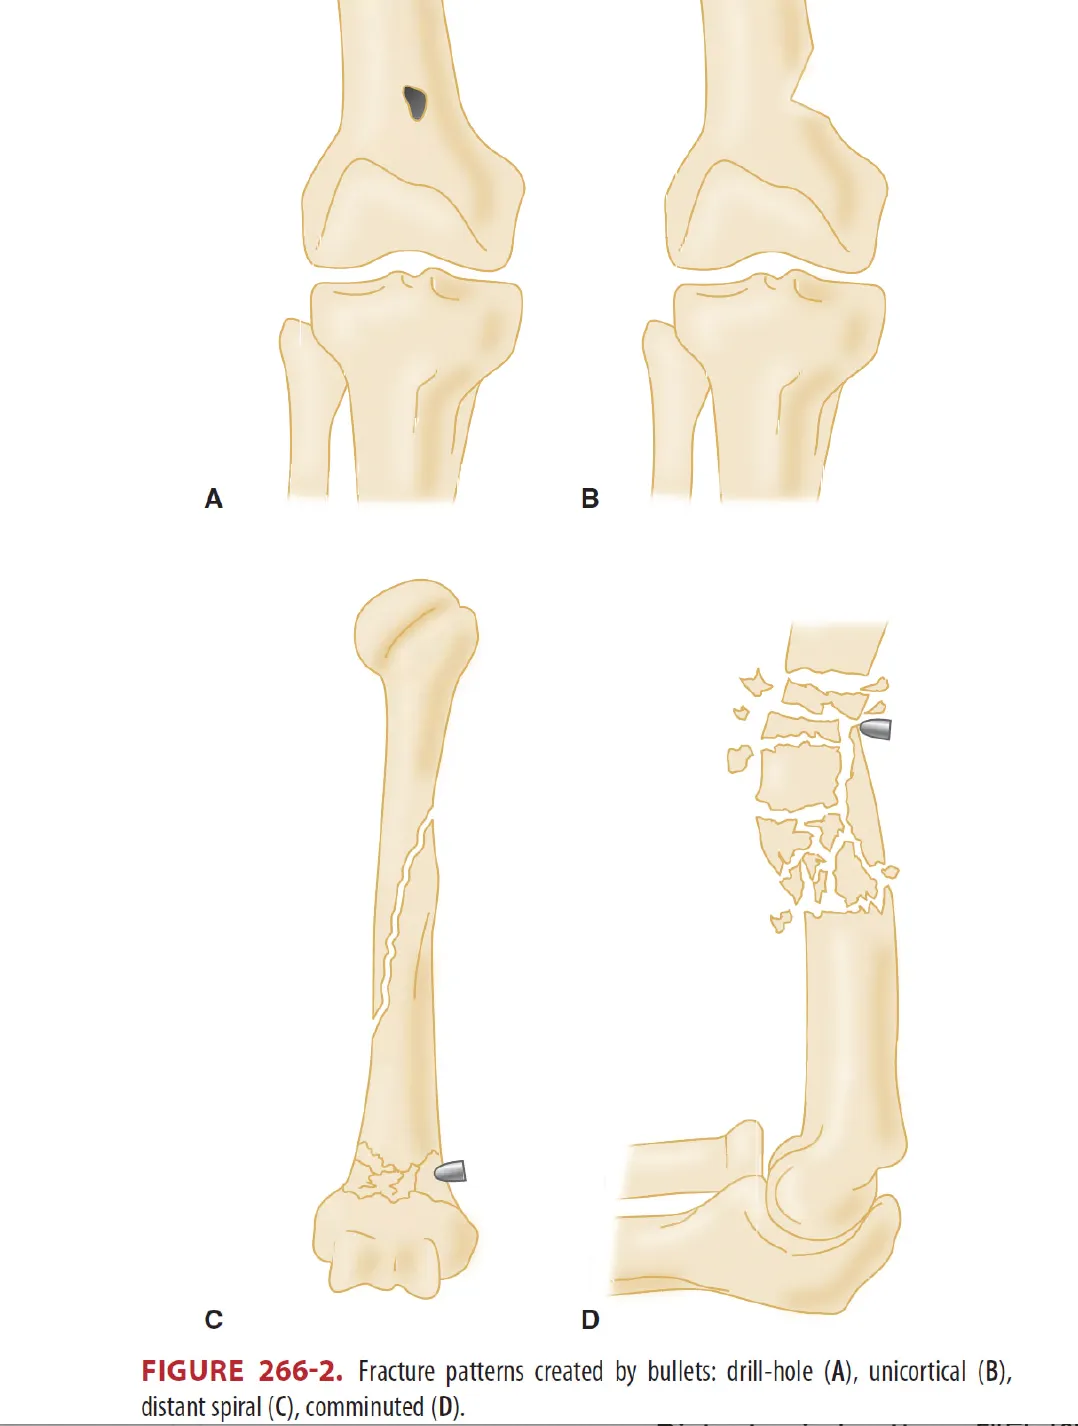

* 그림 266-2. Low energy 총상에서 발생 가능한 4가지 유형의 골절을 나타냄.

266-2. (A) 패턴

: Drill-hole pattern, 다공성이며 저밀도 해면골에서 주로 나타난다.

: 원위 대퇴골, 골반 및 근위 상완골에서 가장 흔함.

266-2. (B) 패턴

: Unicortical pattern, Long bone의 metaphysis에서 주로 관찰됨.

266-2 (C) 패턴

: Distant spiral pattern, 대퇴골에 호발한다.

: 총탄에 의한 직접 손상 혹은 손상 후 낙상 등에 의한 2차적 손상의 가능성이 있다.

266-2. (D) 패턴

: Comminuted pattern 인데 diaphyseal bone에서 주로 관찰되며 다발성 골절이 흔함.